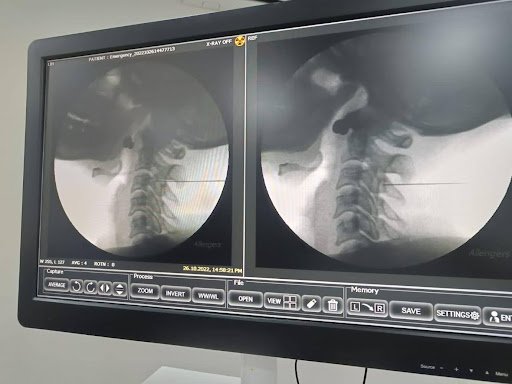

Patient undergoing interlaminar cervical epidural injection under fluoroscopy at Alleviate pain Clinic , Bengaluru. Image Courtesy- Alleviate

- Fluoroscopy-guided cervical epidural injections– reduce nerve inflammation.